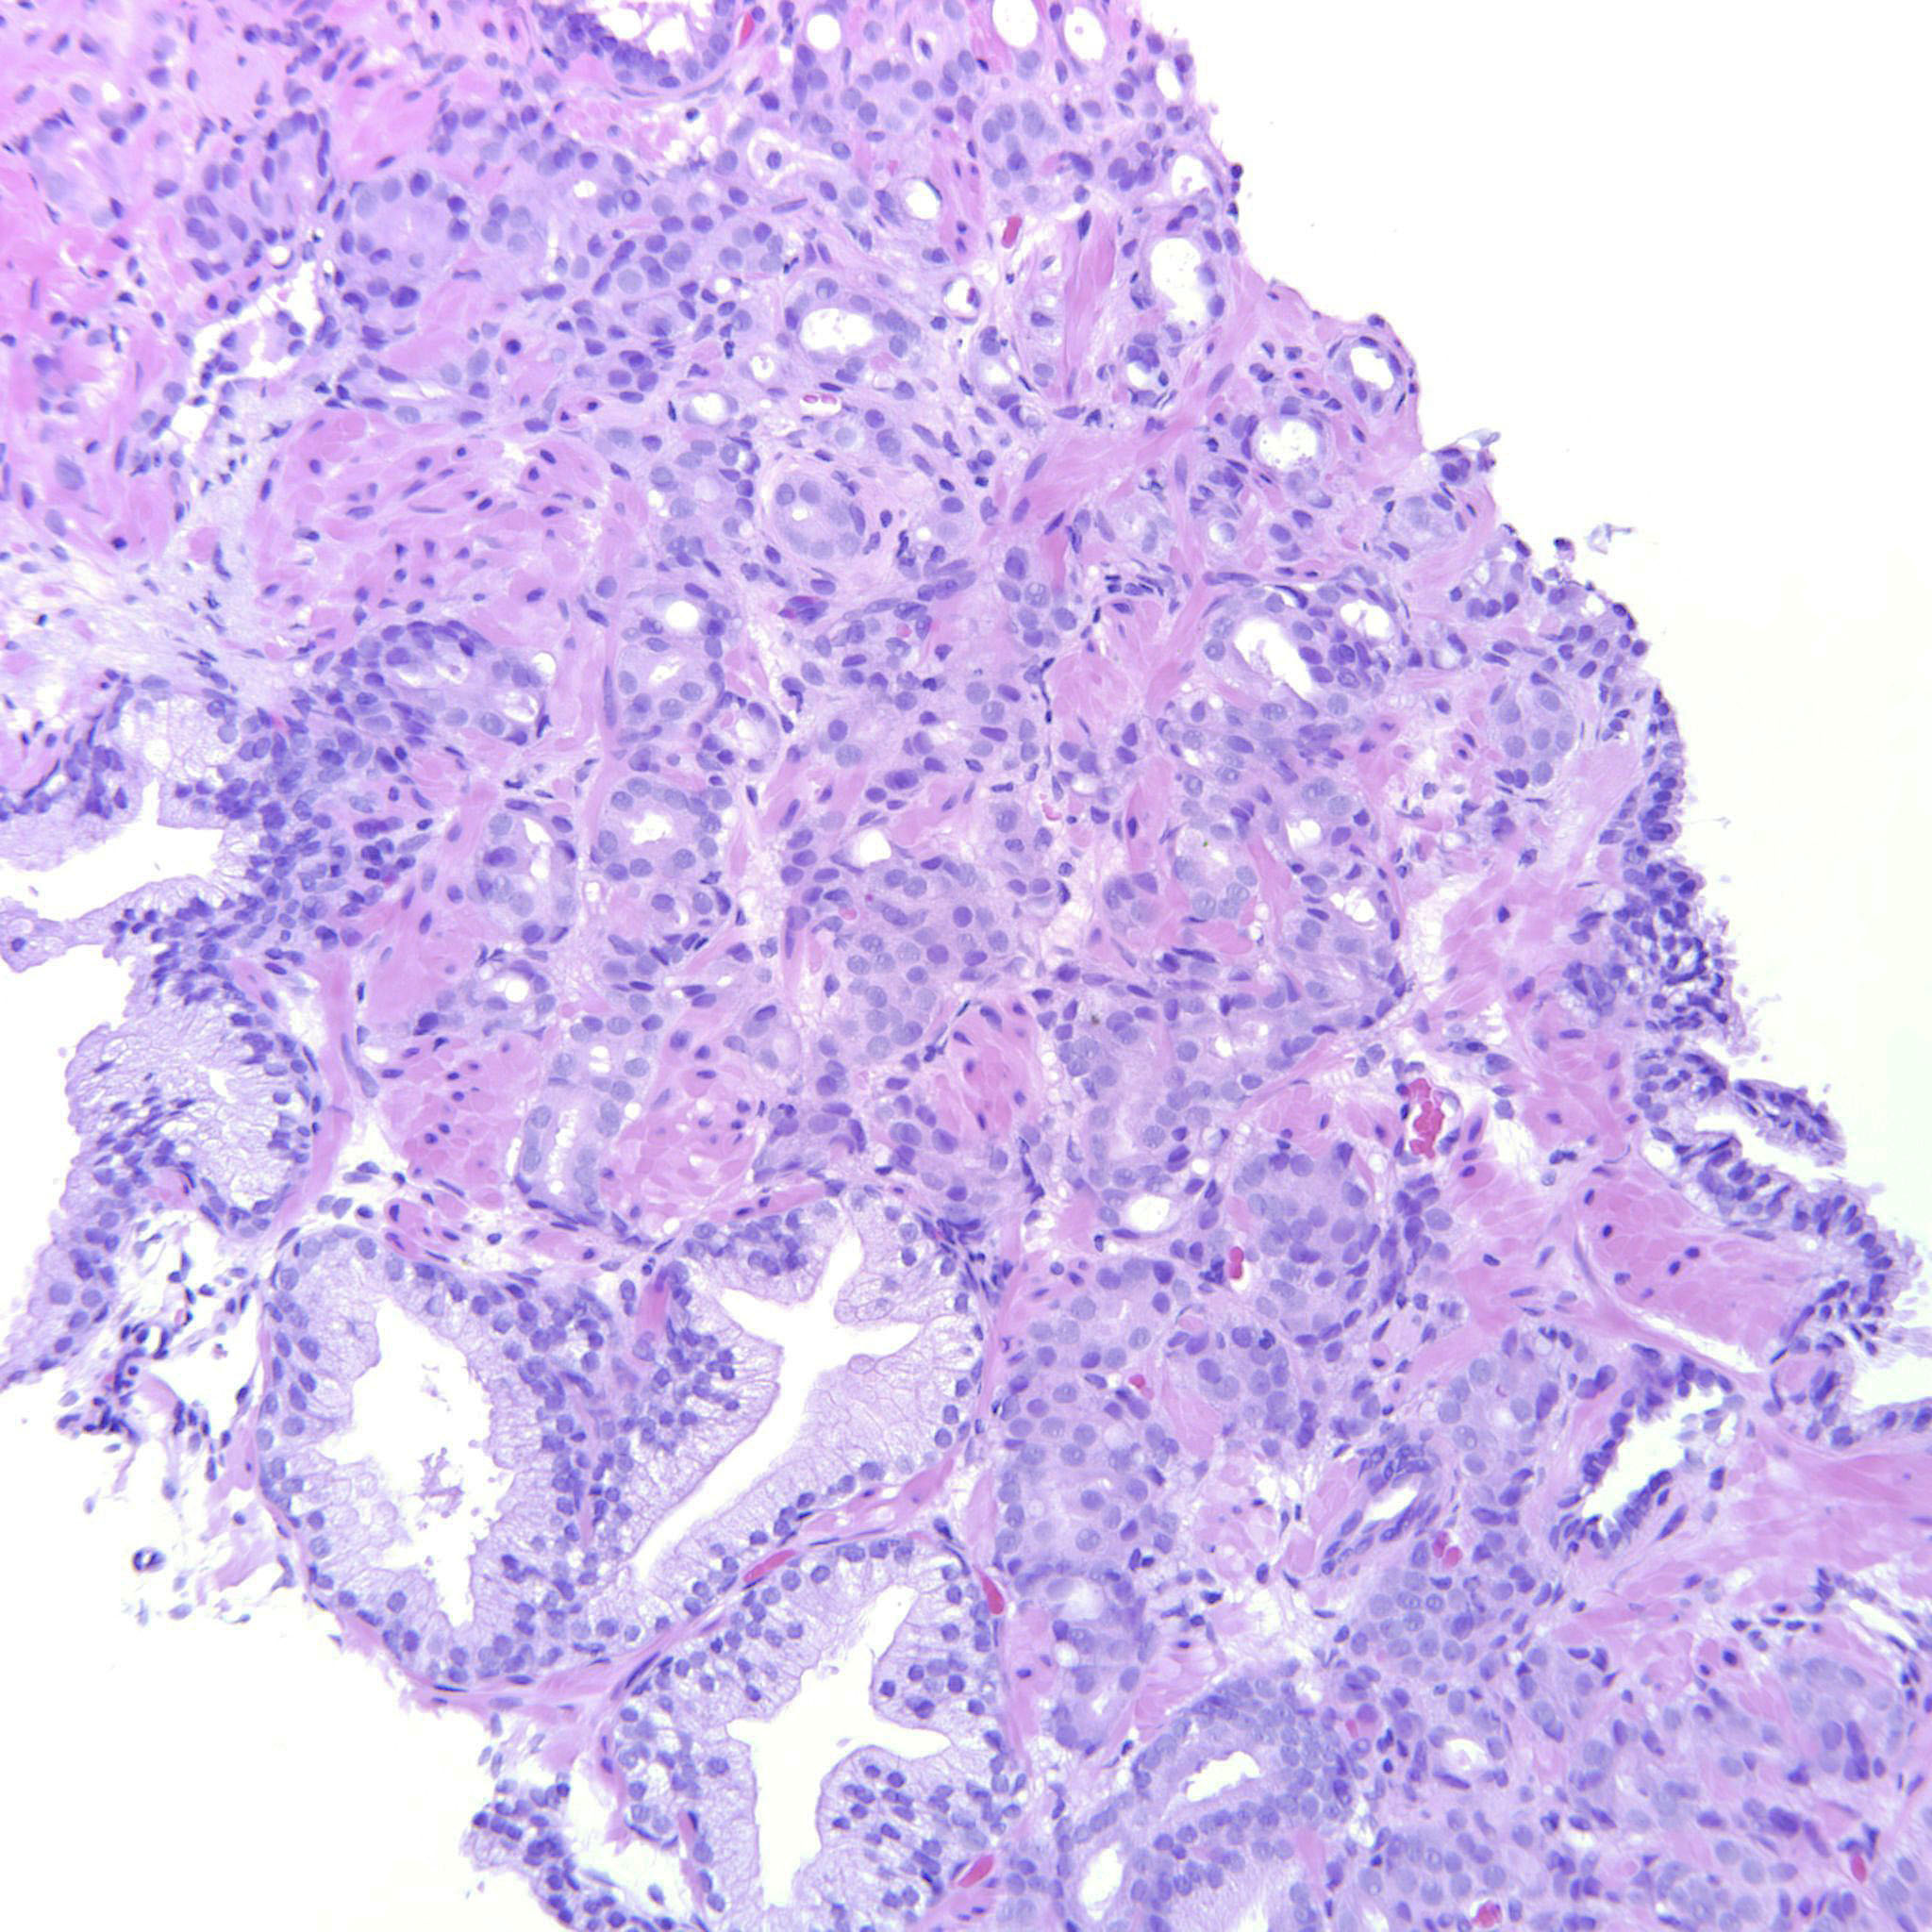

Prostate cancer grading

Case ID: 487